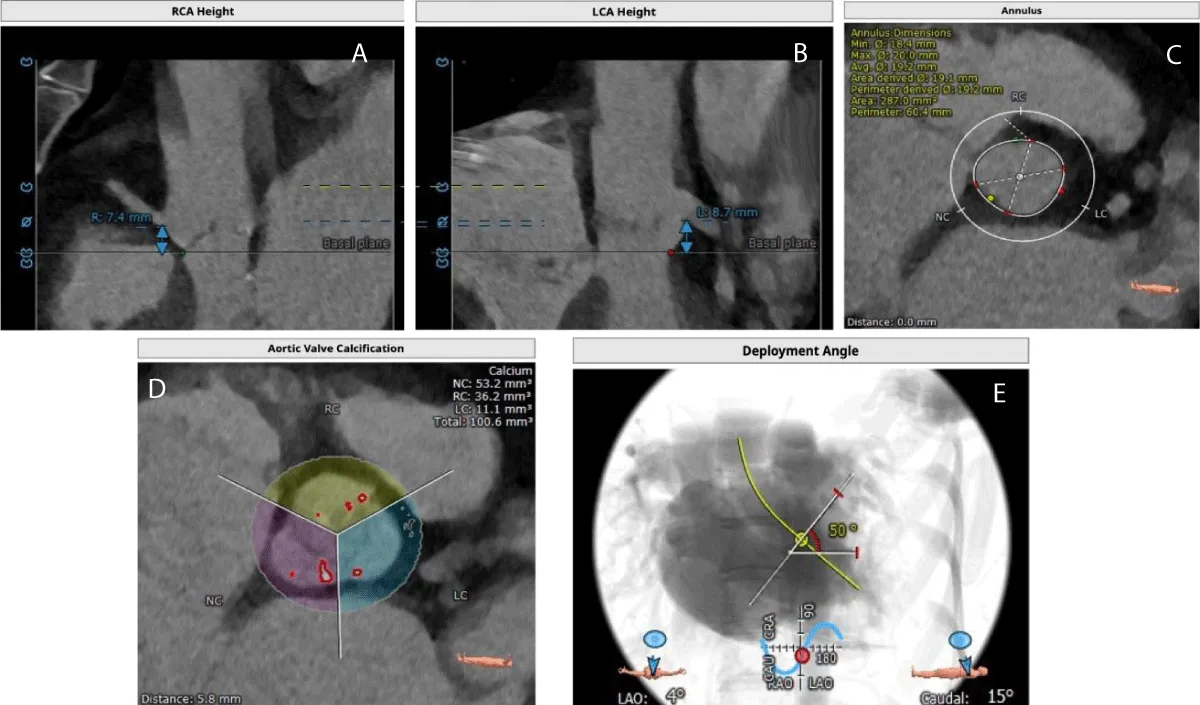

Download Image

The TAVR was performed in the patient under conscious sedation and angiographic imaging guidance with transthoracic echo-doppler monitoring. The right and left femoral arteries, and right femoral vein were cannulated. Through the right femoral vein access, the Temporary Pacemaker (TPI) was positioned in the right ventricle. As a marker for valve installation and to permit arteriography for positioning during the TAVR treatment, a 6-Fr graded pigtail catheter was inserted into the noncoronary sinus via the right femoral artery. Following the completion of all arterial and venous accesses, intravenous unfractionated heparin was delivered to achieve the necessary activated clotting time of > 250 s. The right femoral artery was used to insert a soft 0.035”- J-tipped wire into the descending thoracic aorta followed by performing a pre-closure using a single suture-mediated closure device (Perclose ProGlide®, Abbott Laboratories, Abbott Park, IL, USA) while maintaining arterial access through the J-tipped guidewire. Serial dilatations were performed using the 10-Fr/12-Fr dilator, which was followed by the insertion of the 14-Fr Python Introducer Sheath into the right femoral artery. To cross the valve, a 6-Fr AL-1 catheter was inserted through the valve delivery sheath, and a 0.035”- J-tipped guidewire was inserted and swapped for a 0.035 - inch straight-tip wire (Radiofocus® Guidewire M, Terumo Corporation., Tokyo, Japan). After crossing, the straight-tip wire was replaced with a 300-cm J-tipped wire following which, the AL-1 catheter was withdrawn and replaced with a 6-Fr angled pigtail catheter. Subsequently, a stiff guidewire SAFARI 2™ (Boston Scientific, Marlborough, MA, USA) was inserted through the angled pigtail catheter into the left ventricle with the guidewire’s transition point held above the apex and pointing away from the ventricular wall. A 20 mm BE Myval THV implant was crimped over the Navigator THV delivery system and deployed with rapid pacing through the TPI (Figure 2). Immediately after the procedure, peak and mean PG improved to 30 mmHg (baseline: 61 mmHg) and 16 mmHg (baseline: 38 mmHg), respectively.

Figure 2: Angiographic images of Myval THV Implantation- A) Baseline Aortogram, B) Myval THV Navigation, C) Myval Deployment and D) Final aortogram with no PVL.